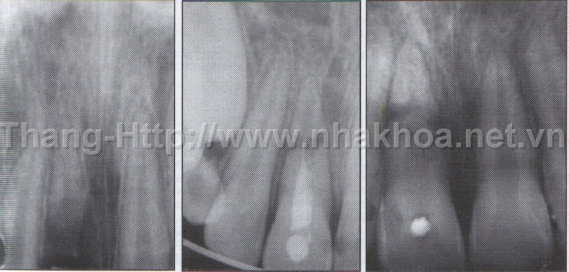

Ở người trẻ tuổi, tủy răng có thể phục hồi sau chấn thương, tùy mức độ sang chấn tủy răng mà bác sĩ có thể quyết định lấy tủy răng hoặc không và thường khuyên giảm tối đa tác động lên răng bị chấn thương. Để giúp tủy phục hồi, nên ăn thức ăn mềm, tránh uống nước quá lạnh hoặc quá nóng. Tuy nhiên, có nhiều trường hợp sau 5-8 năm bị chấn thương, răng mới có triệu chứng sưng đau, hoặc đổi màu. Khi đó, cần điều trị tủy và những sang thương ở chóp răng.

Gãy thân răng không lộ tủy

Nên giảm tác động mạnh trên răng, theo dõi tủy răng và chỉ lấy tủy khi răng bị sưng, đau. Thường sau 3 tuần bị chấn thương, nha sĩ mới thực hiện việc trám tái tạo thân răng.

Trường hợp lộ tủy, chảy máu từ vết gãy, răng chưa đóng chóp đủ, nên đến nha sĩ điều trị tủy và băng tạm ống tủy 3-9 tháng hoặc 1-3 năm, đến khi răng đóng chóp mới trám bít tủy răng hoàn chỉnh. Lưu ý các răng đã lấy tủy rất dễ vỡ nếu va chạm vật cứng. Vì vậy việc cần làm càng sớm càng tốt sau chữa tủy răng là làm mão bọc gia cố cho toàn bộ thân răng và phục hồi lại vẻ thẩm mỹ của vùng thân răng bị gãy, vỡ.